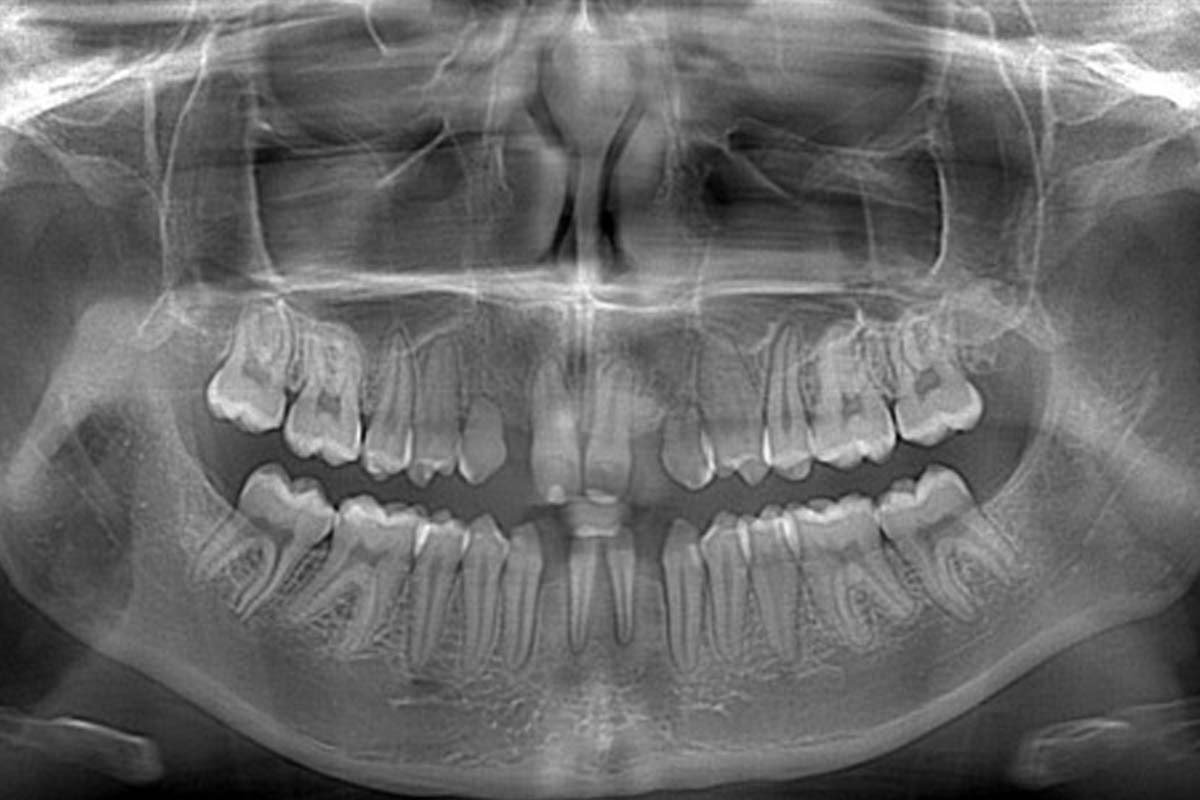

Early dental screening helps identify jaw and teeth alignment issues in children at an early stage. Timely orthodontic care can prevent complex treatments and jaw surgery later in life while improving oral health and confidence.